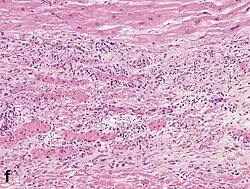

Although earlier changes can be discerned using electron microscopy, one of the earliest changes under a normal microscope are so-called wavy fibers.[23] Subsequently, the myocyte cytoplasm becomes more eosinophilic (pink) and the cells lose their transversal striations, with typical changes and eventually loss of the cell nucleus.[24] The interstitium at the margin of the infarcted area is initially infiltrated with neutrophils, then with lymphocytes and macrophages, who phagocytose ("eat") the myocyte debris. The necrotic area is surrounded and progressively invaded by granulation tissue, which will replace the infarct with a fibrous (collagenous) scar (which are typical steps in wound healing). The interstitial space (the space between cells outside of blood vessels) may be infiltrated with red blood cells.[22]

Neutrophil infiltration | 12–24 h | 1–3 days | 5–7 days | ![]() |

Macrophages and lymphocytes | 3–5 days | 5–10 days (including 'siderophages') | 10 days to 2 months | ![]() |